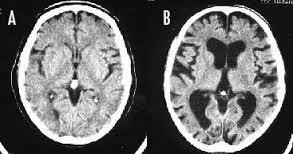

「喫煙者の脳」やはり異変が起きていた ・タバコを吸うと大脳皮質が薄くなる ・タバコを吸うと認知機能が落ちる ※写真は左Aが正常の脳、右Bが喫煙者の脳です。 左の脳と比べて右の脳は隙間だらけになってしまってします。

--- 「喫煙者の脳」やはり異変が起きていた(石田雅彦) - Yahoo!ニュース ---

タバコを吸うと脳がすっきりするのは真っ赤な嘘だ。研究によれば喫煙者の脳では明らかに異常が起きている。認知機能も低下し、大脳皮質が元に戻るのには25年もかかる。一刻も早くタバコなど止めたほうがいい。